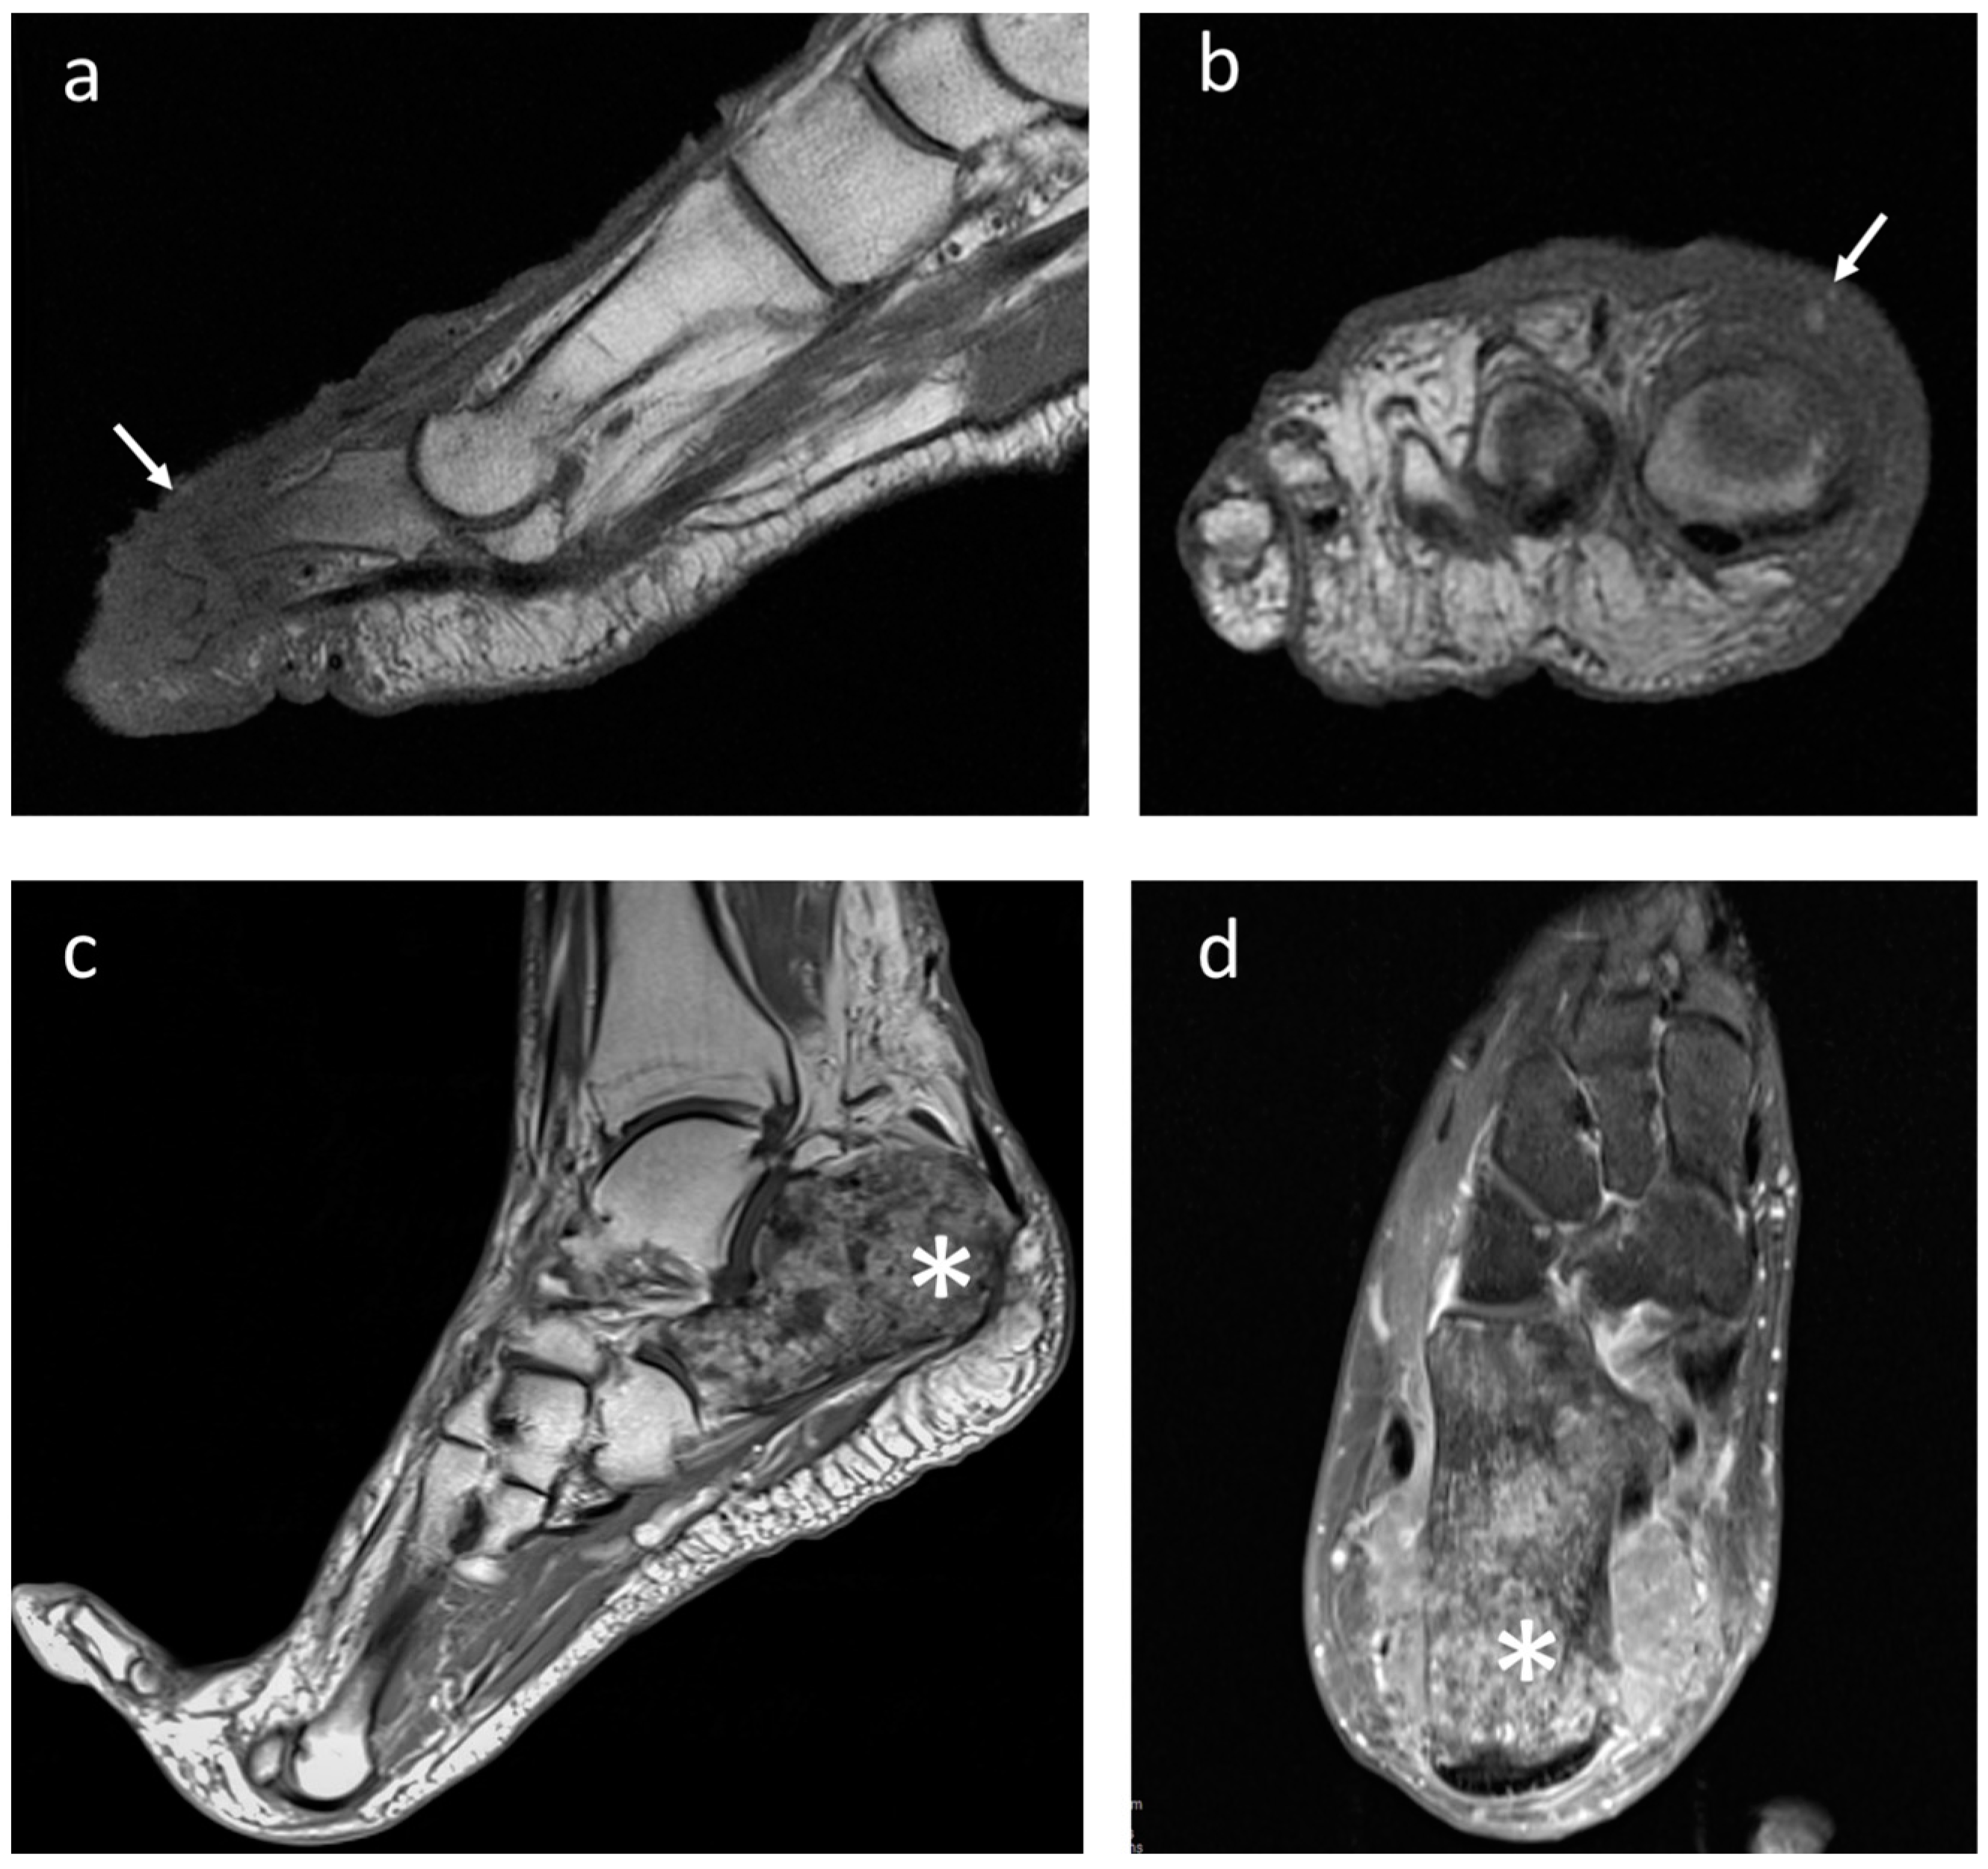

4.4. Clear-Cell Sarcoma

4.5. Rhabdomyosarcoma